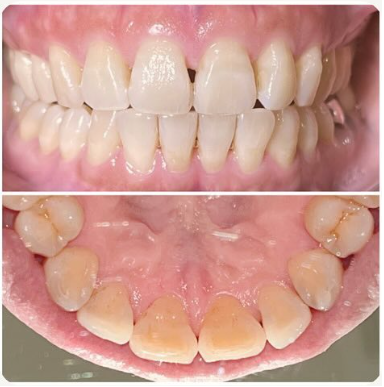

ステイン除去

BEFORE

AFTER

年齢:40代女性

治療内容:エアーフローによる歯の着色汚れ、ステイン除去

治療期間/通院回数:1回

費用: ステインコース 8,800円

リスク・副作用

①効果には個人差があり、着色汚れによっては一度に取りきれない場合があります。

施術後数時間以内に、着色効果の強いもの(コーヒー・紅茶・喫煙など)を摂取すると、歯に色素沈着が起こる可能性があります。

パウダーの刺激により歯ぐきから出血する可能性があります(痛みはほとんどありません)。